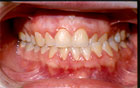

La mordida abierta anterior esquelética (Fig. 3), las sobremordidas horizontales de más de 6mm. (Fig. 4), una distancia mayor de 4mm. desde relación céntrica a máxima intercuspidación, mordida cruzada unilateral (Fig. 5 y 6) y ausencia de sectores posteriores de 5 ó más piezas, han sido los factores oclusales que se han asociado con grupos de diagnóstico específicos en disfunción de la ATM.

Fig. 3 Mordida Abierta

Fig. 4 Resalte

Fig. 5 Mordida Cruzada

(Vista Lateral)

Fig. 6 Mordida Cruzada

(Vista Frontal)